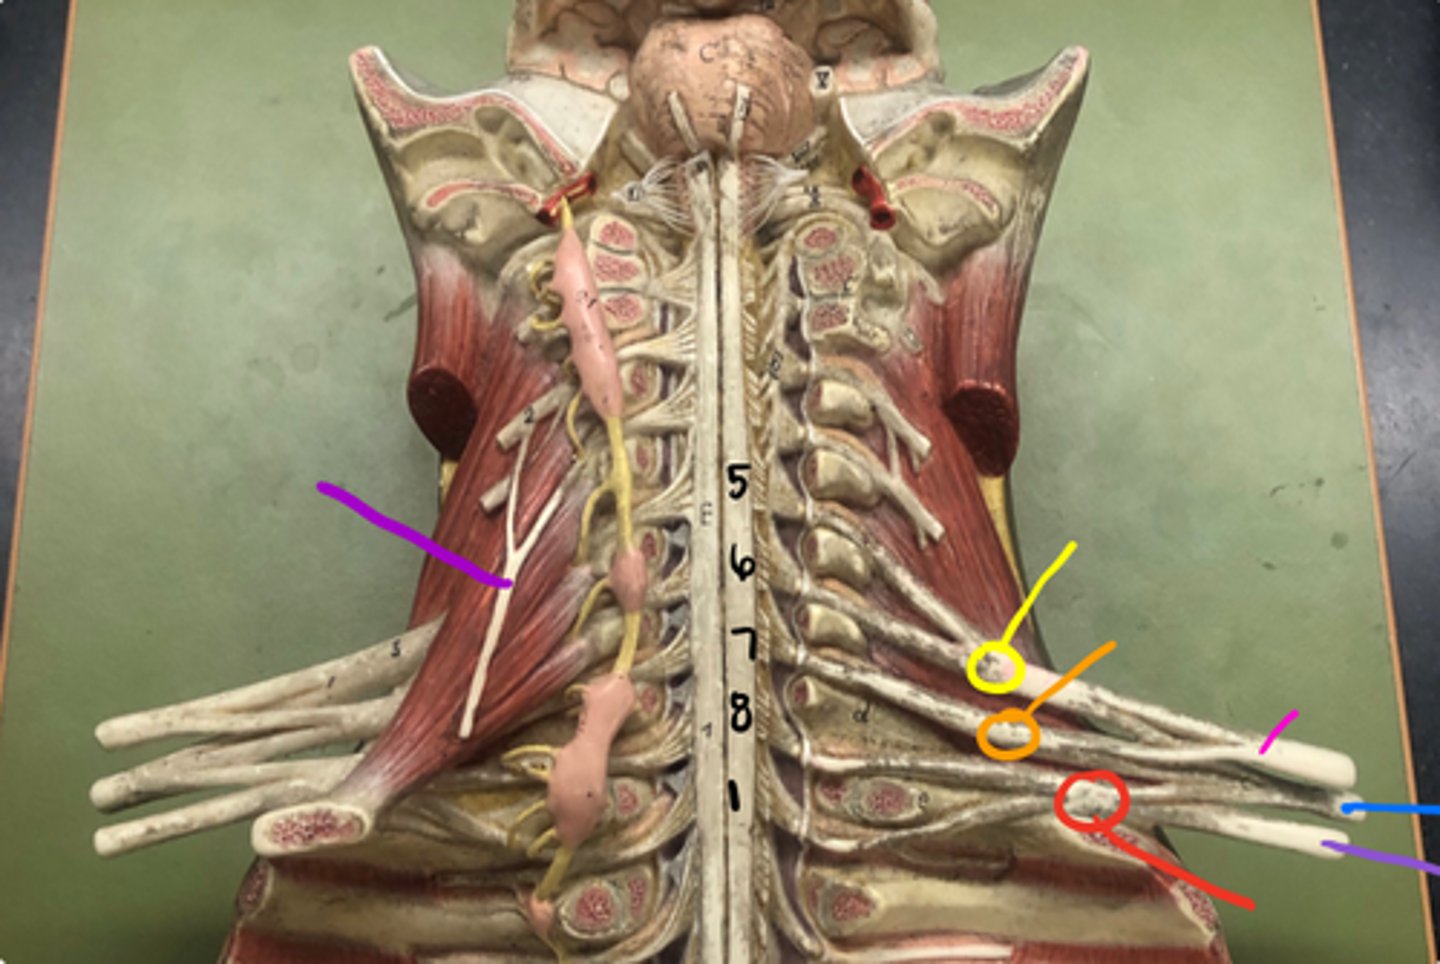

phrenic nerve

neon purple (on neck)

superior trunk

yellow

middle trunk

orange

inferior trunk

red

lateral cord

pink

medial cord

purple

posterior cord

blue